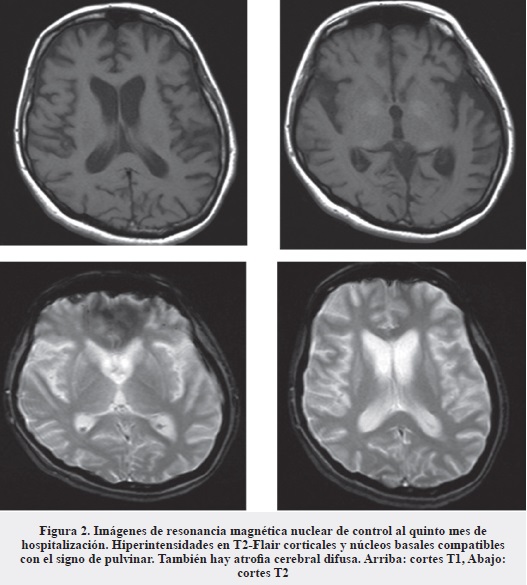

La evolución continúa estacionaria; se solicita nueva RMN cerebral simple y contrastada que muestra hiperintensidades en T2-Flair corticales y núcleo basales, secuelas de probable injuria vascular en núcleo basal derecho, así como atrofia cerebral difusa (Figura 2).

Los hallazgos electroencefalográficos consisten en ondas agudas trifásicas periódicas (13). En las secuencias T2 de la resonancia magnética los hallazgos típicos incluyen hiperintensidades simétricas bilaterales en los ganglios basales (signo del pulvinar), putamen y cabeza del caudado. También son frecuentes las lesiones de la corteza cerebral (14). El análisis de proteína 14-3-3 en líquido cefalorraquídeo tiene una sensibilidad reportada de 92% con especificidad variable según distintas series, pero especialmente baja (82-87%) en otros desórdenes como procesos neurodegenerativos, neoplasias, accidentes vasculares cerebrales, epilepsia y condiciones psiquiátricas (15). Según recomendación del Colegio Americano de Neurología, debe realizarse esta prueba diagnóstica en pacientes con demencia rápidamente progresiva, sospecha clínica de enfermedad de Creutzfeldt-Jakob e incertidumbre diagnóstica (16). El estándar de oro para el diagnóstico es la detección de proteínas priónicas (PrPSc) en biopsias cerebrales o autopsia.